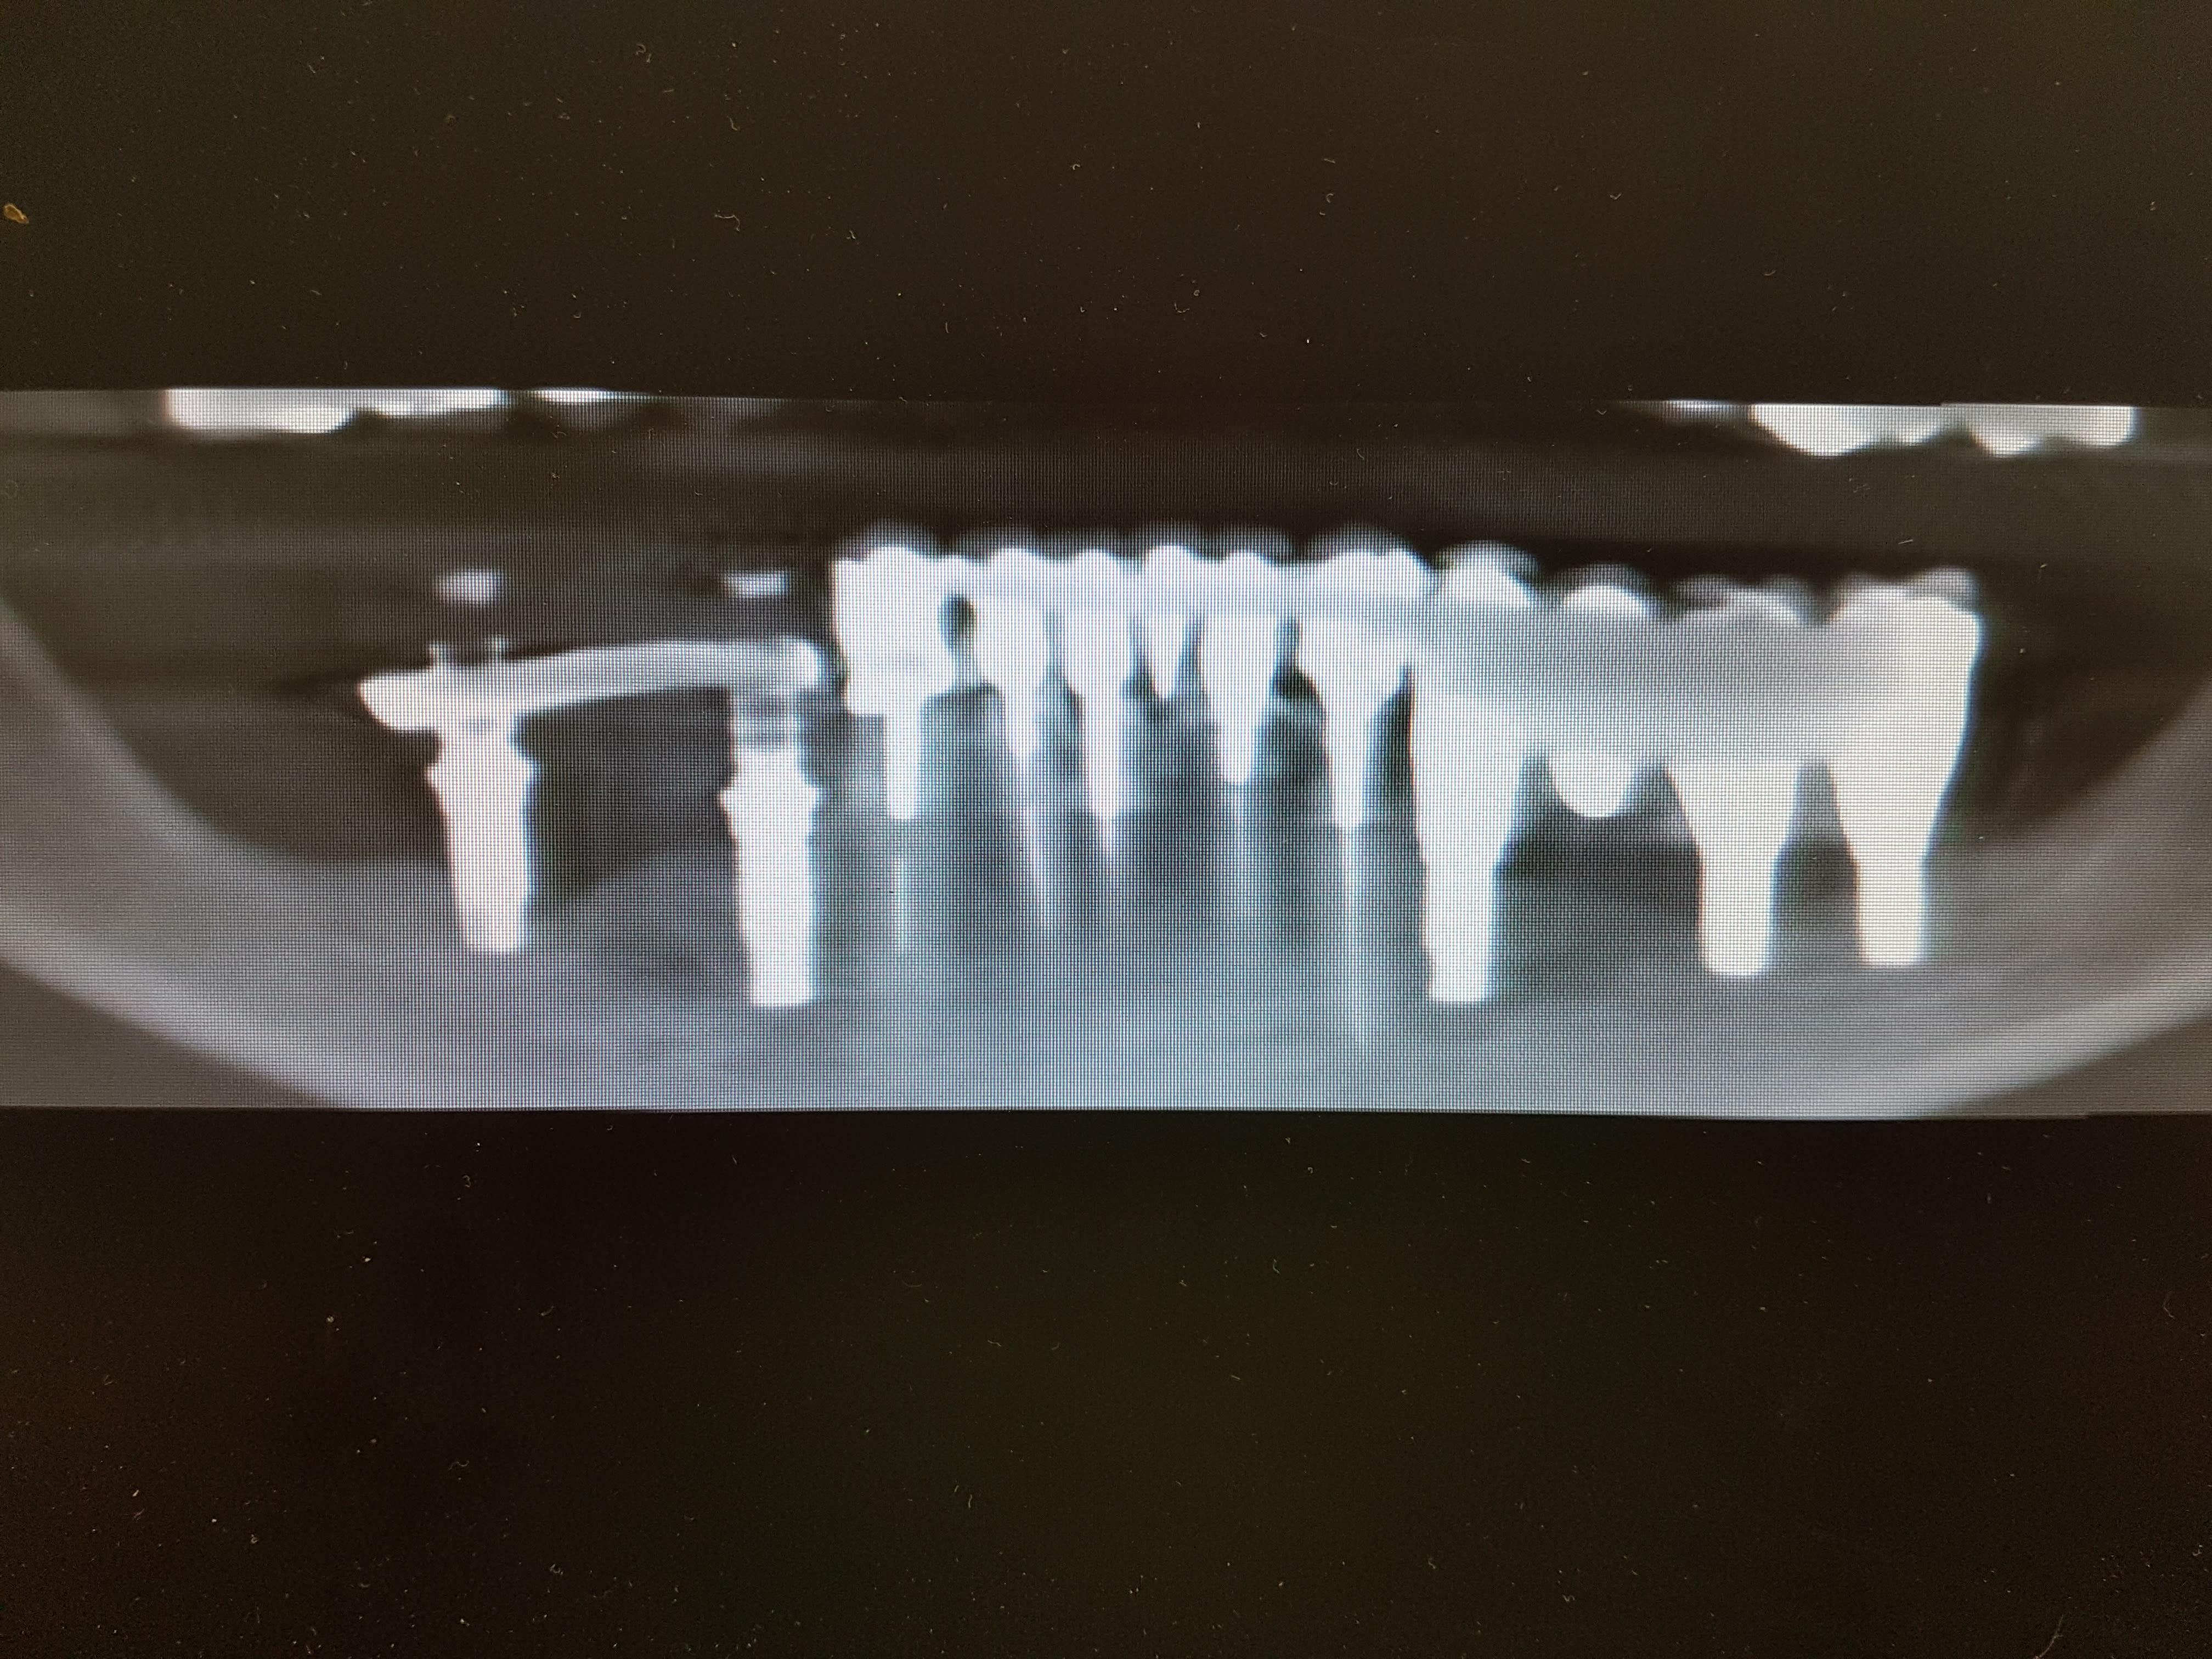

prélevements au menton et au ramus pour des greffes dans les secteurs III et IV puis pose d'implants en 34 , 36, 37 , 44 , 47 . bridge ceramo metal scellé 34 à 37 et bridge provisoire sur MUA toujours en place sur 44-47 . tout ceci a été réalisé il y a environ 2 ans .

divers problèmes sont apparus rapidement : perte de sensibilité partielle secteurIV toujours pas revenu à la normale et apparition d'un abcès au niveau de 36 il y a un an environ suivi d'un curetage au même endroit que celui pour lequel je voyais le patient en urgence .

j'ai revu le patient la semaine dernière qui voulait que je prenne la suite . j'ai fait un scan et voilà ce que çà donne .